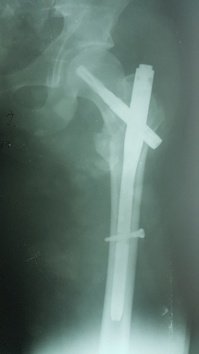

При огляді: положення хворого пасивне на каталці, біль в області в\3 правої стегнової кістки та кульшового суглобу що посилюється при пальпації та спробі рухів у суглобі. Крепітація уламків. Права н\кінцівка ротована до зовні. Позитивний симптом «прилиплої п’яти». Проведено рентгенографію правої стегнової кістки з кульшовим суглобом. Встановлено діагноз: Закритий уламковий, черезвертельний перелом правої стегнової кістки (Клас АО 31.А2.2) зі зміщенням.

Хворий госпіталізований в травматологічне відділення для подальшого дообстеження та оперативного лікування. З метою тимчасової фіксації, тракції та зменшення больового синдрому накладено систему скелетного витяжіння. В умовах травматологічного відділення хворий був дообстежений та оглянута суміжними спеціалістами терапевтом, кардіологом, анестезіологом.

Протягом 32 годин від отримання травми хворий був прооперований. Операція: Закрита репозиція з металоостеосинтезом перелому 31.А2.2 проксимальним стегновим стрижнем PFN-A. Після оперативного втручання хворий перебував під наглядом у відділенні інтенсивної терапії. На 2гу добу хворий переведена в травматологічне відділення. В травматологічному відділення хворому під наглядом лікуючого лікаря було дозволено сідати у ліжку. На 3 тю добу хворий під наглядом лікуючого лікаря з допомогою вставав. На 4-ту добу пересувався біля ліжка в палаті. На 5 ту-10ту добу хворий пересувався з допомогою в ходунках в межах палати. На 12 ту добу знято шви з рани. Хворий в задовільному стані виписаний з травматологічного відділення. На амбулаторне лікування. Надано рекомендації з приводу подальшого лікування в амбулаторних умовах.